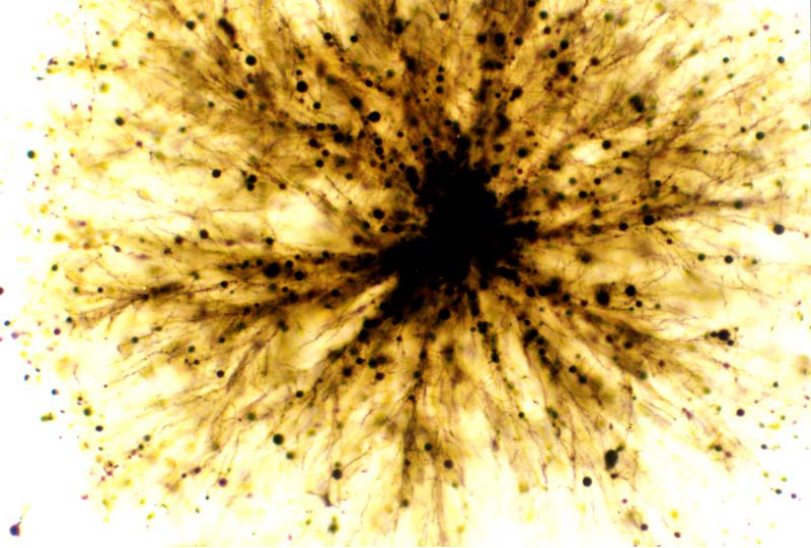

纤维性星形胶质细胞光镜像:

原浆性星形胶质细胞光镜像:

少突胶质细胞光镜像:

小胶质细胞光镜像: